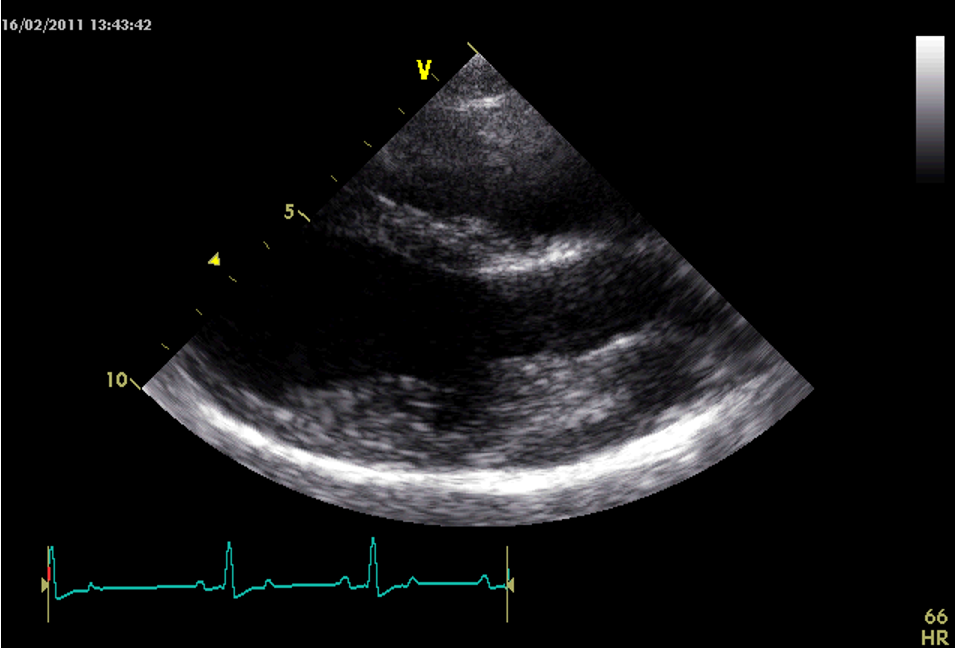

Q

Which view is this?

A

Right parasternal short axis view LV @ pap mm level

Right ventricle small at the top.

Left ventricle dominating in the middle.